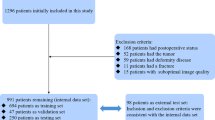

Cervical spine CT images of 685 patients were divided into a training (n = 548) and a test set (n = 137). The training set was used to develop a VB-Net DL model, including a 3D segmentation model of multiple cervical spine subregions and a key point location model on the midsagittal slice of the cervical spine CT. The parameters measured included sagittal vertebral canal diameter (SCD), sagittal vertebral body diameter (VBD), Pavlov’s ratio, transverse vertebral canal diameter (TCD), and osseous spinal canal area (OSCA). Manual measurements were performed by a radiologist and a spinal surgeon. The model’s performance was evaluated using the Mann–Whitney U test, Pearson correlation, mean absolute error, and Bland–Altman plots.